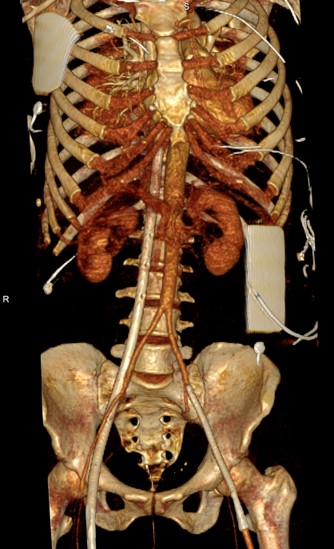

Weird appearance of aorta on CTA. Can easily be confused with dissection, but this is from contrast mixing with blood return in VA ECMO. The 3D image shows ECMO canulae. Several nice references, here's one from Korea https://www.ncbi.nlm.nih.gov/pmc/articles/PMC4023050/ …

#FOAMed#radres pic.twitter.com/doTpBuhMDl